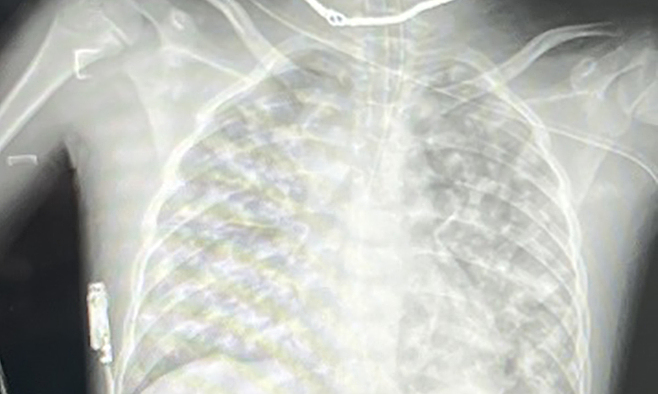

Phim Xquang chụp phổi của bệnh nhi lúc mới nhập viện cho thấy tình trạng viêm phổi rất nặng. Ảnh: Bác sĩ cung cấp